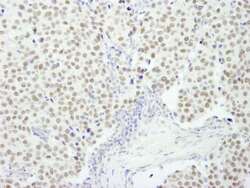

Supportive validation

- Submitted by

- LSBio (provider)

- Enhanced method

- Genetic validation

- Main image

- Experimental details

- Detection of Human RCOR3 by Immunohistochemistry. Sample: FFPE section of human breast carcinoma. Antibody: Affinity purified rabbit anti-RCOR3 used at a dilution of 1:250.

- Submitted by

- LSBio (provider)

- Enhanced method

- Genetic validation

- Main image

- Experimental details

- Detection of Human RCOR3 by Immunohistochemistry. Sample: FFPE section of human prostate carcinoma. Antibody: Affinity purified rabbit anti-RCOR3 used at a dilution of 1:250.